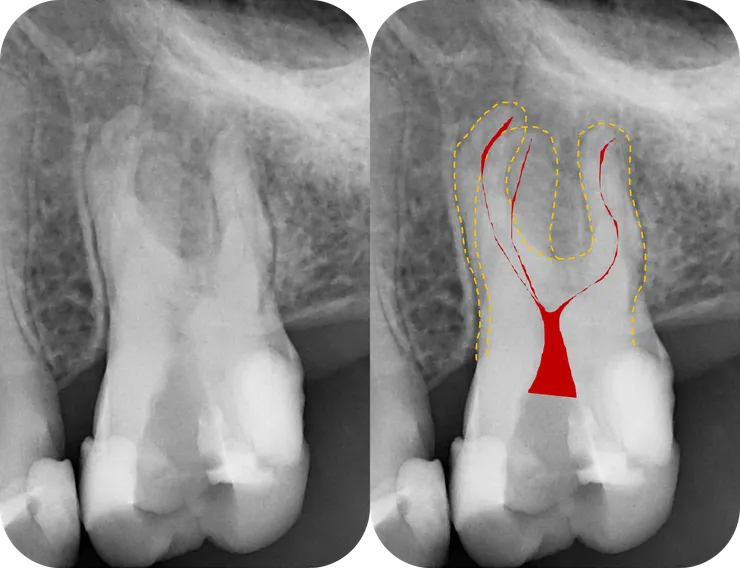

面對這種一看就知道絕非善類的 case, 最關鍵的步驟就是,在開始之前先仔細地把目標物清楚地描繪一番:

先如同橘色虛線般,將 root 的外型描繪出來 (相對單純的 palatal root 先忽略)。

然後再依據 root 的外型,將依稀可見的 canals 如同紅色線條般描繪出來。

腦中有了清晰的圖像後,才能以終為始的,一步步地完成後續的修形與封填。

(當然前提是必須有清晰的 initial PA, 而如果能藉由 CBCT 得到立體的架構那更好!)